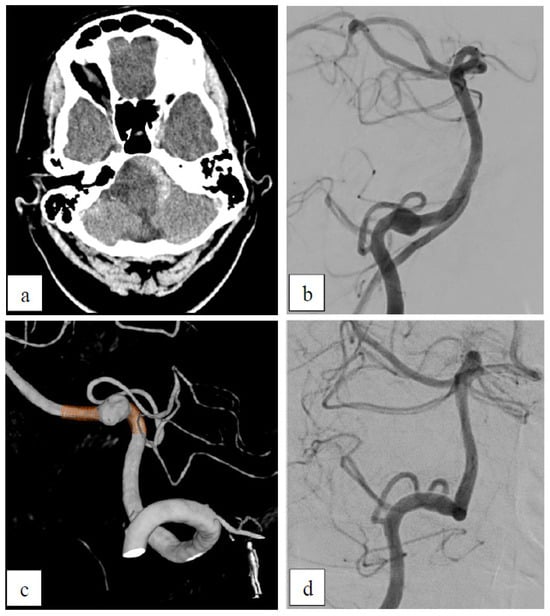

Case 5: Inflammatory Aneurysm

| 5 | 67 | m | AICA (two aneurysms) | right | inflammatory | yes (SAH) | no | ASA | prox:B3 dist: A3 | - | - |